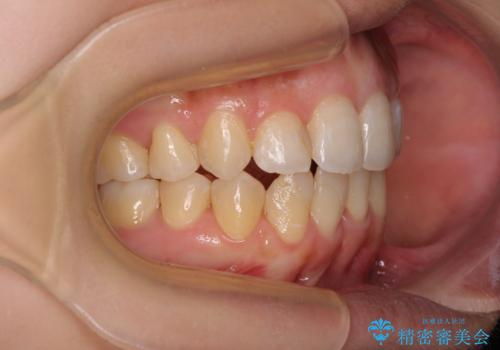

後戻りの再矯正 ワイヤー装置でデコボコと隙間を改善

- 学生時代の抜歯矯正の後戻りが気になり、再矯正を希望して来院された患者様です。

マウスピース矯正は継続する自信がなく、気になるところを短期間で改善したいとのことで、ワイヤー装置にて矯正治療を行うこととしました。

詰め物で隠していた下顎前歯の隙間は、歯軸を改善することで詰め物を除去しても隙間が目立たなくなりました。

まだ改善したいところはありましたが、患者様自身は大変満足されたとのことで、治療を終えることとなりました。